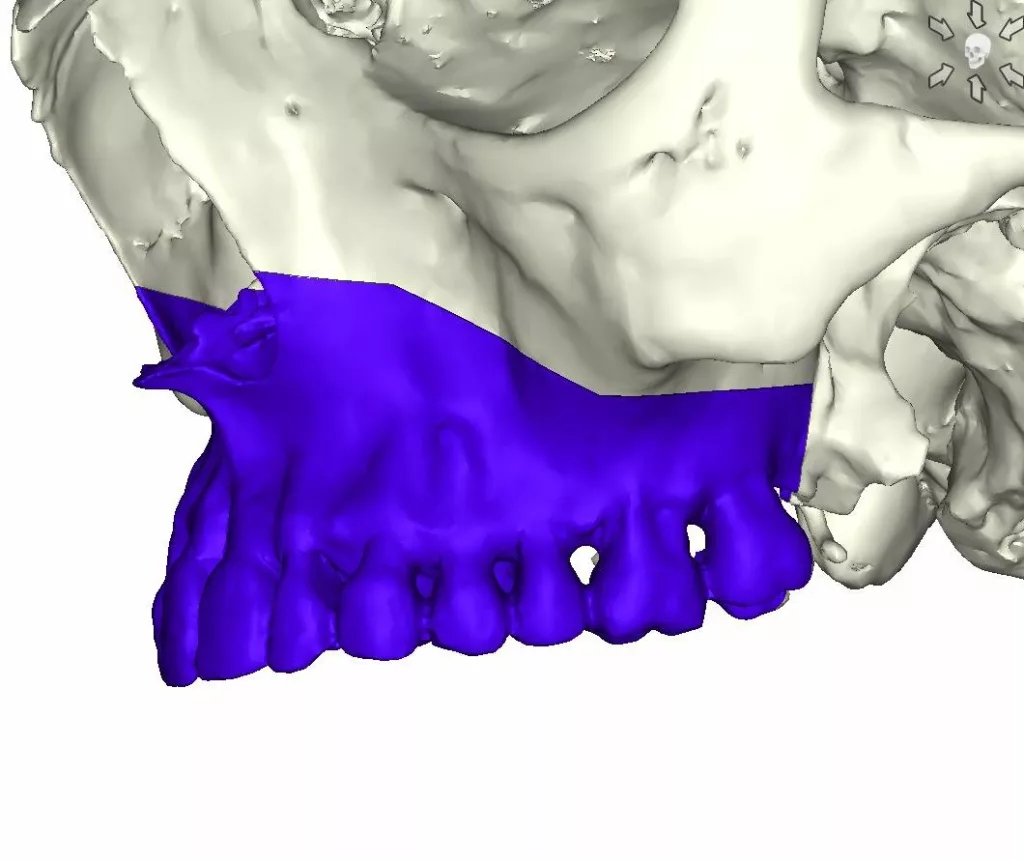

La Chirurgie assistée par ordinateur, guides et plaques sur mesure

On l’appelle plus communément « chirurgie guidée »

La chirurgie guidée consiste à simuler le geste opératoire au moyen de logiciels spécialisés puis à assurer le contrôle de l’exécution chirurgicale au bloc opératoire à l’aide de guides de découpe osseuse et de forage.

Des miniplaques en titane sur mesure spécifiques de l’anatomie propre à chaque patient et spécifiques des mouvements envisagés par le chirurgien permettent de stabiliser toutes les pièces anatomiques libérées par les manœuvres d’ostéotomie conformément à la simulation : plateau maxillaire, arc denté mandibulaire, branches montantes et condyles, menton .

Ostéotomie de Lefort I en 1, 2 ou 3 fragments, ostéotomie sagittale des branches montantes, génioplasties, ostéotomies segmentaires maxillaires et mandibulaires, postérieures ou antérieures, plus rarement ostéotomies de Lefort II ou Lefort III, tous les types d’ostéotomies peuvent être réalisés en chirurgie guidée.

La chirurgie guidée présente d’autres avantages :

- la compréhension de la dysmorphose dans toutes ses composantes basales et alvéolaires permet au chirurgien de proposer des mouvements radicaux correspondants aux besoins fonctionnels et esthétiques

- le contrôle de l’exécution, en l’absence d’évènement indésirable toujours possible, permet d’établir un véritable « contrat de soin » avec le patient mis en confiance

Quelques règles cependant doivent être connues à propos de la chirurgie guidée intégrale:

- la chirurgie guidée requiert un bilan scanner pré-opératoire complet de l’extrémité céphalique

- puisque toutes les pièces squelettiques peuvent être positionnées dans les trois dimension de l’espace selon les choix du chirurgien, la stratégie prime sur l’exécution

- une analyse céphalométrique de la situation pré-opératoire et une analyse céphalométrique de la simulation, confrontées à la situation clinique du patient et à ses aspirations sont obligatoires. Pour notre part, nous utilisons l’analyse céphalométrique de Jean Delaire qui nous semble, jusqu’à preuve du contraire, la plus performante

- la simulation de l’acte opératoire est un acte médical qui appartient au chirurgien et à lui-seul. Responsable médicalement et juridiquement du patient qui lui a accordé sa confiance, il ne peut faire réaliser la simulation par un tiers qu’il soit chirurgien ou non chirurgien. Avant la fabrication des guides et des plaques, l’industriel fait signer au chirurgien un document engageant sa responsabilité

- la chirurgie guidée engendre un surcoût financier dont doit être informé le patient (ingénieurs biomédicaux en charge du design des guides et des plaques sous la responsabilité du chirurgien, fabrication industrielles des guides et des plaques sur mesure).

- Aucun mouvement orthodontique ne peut être réalisé une fois que le scanner préopératoire de l’extrémité céphalique a été réalisé

Il s’agit d’une technique nouvelle mais qui appartient déjà aux données acquises de la science

Particulièrement performante, nous utilisons la chirurgie guidée intégrale Delairienne depuis quinze années.